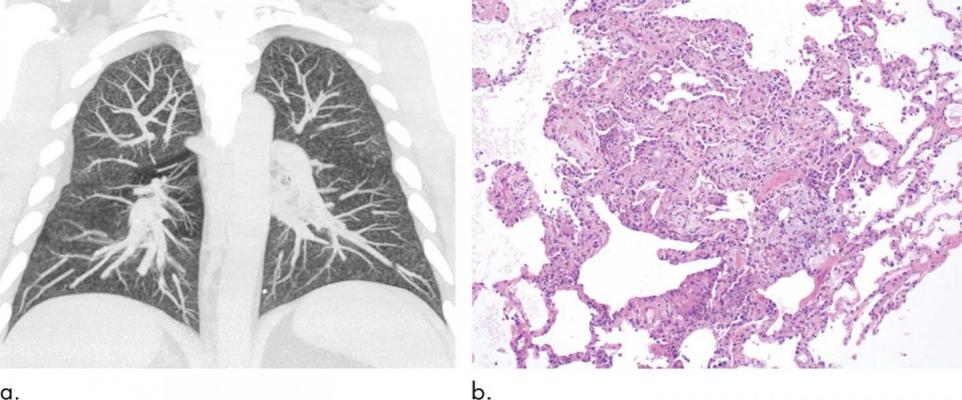

Images show electronic cigarette or vaping product use-associated lung injury in a 32-year-old man with history of vaping who presented with fevers and night sweats for 1 week. (a) Coronal maximum intensity projection image shows diffuse centrilobular nodularity. (b) Histologic sections of his transbronchial cryobiopsy showed distinctive micronodular pattern of airway-centered organizing pneumonia, corresponding to centrilobular nodularity seen at CT. Similar imaging and pathologic findings have been described in patients with smoke synthetic cannabinoids. Image courtesy of Radiological Society of North America (RSNA)

Patients with EVALI typically have a combination of respiratory and gastrointestinal symptoms, as well as general symptoms like fever or fatigue. Chest CT findings in EVALI can be variable but most commonly show a pattern of diffuse lung injury with sparing of the periphery of the lungs. EVALI is a diagnosis of exclusion. The patient must have a history of vaping within 90 days and abnormal findings on chest imaging, but other possible causes for the patient’s symptoms must be eliminated.